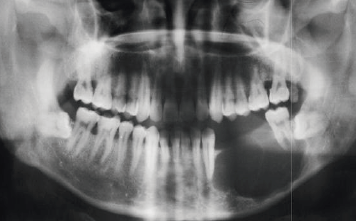

Es la rama de la odontología encargada del diagnóstico y tratamiento quirúrgico de las alteraciones en los tejidos duros y blandos de la boca como patologías infecciosas, tumorales y de malformaciones bucales y maxilofaciales, utilizando como ayudas diagnósticas la imagenología, la histopatología y pruebas de laboratorio clínico.

El odontólogo especialista en esta área posee el conocimiento y la destreza para toma de biopsias, realización de tratamientos de urgencias, manejo de alteraciones de la boca como: frenillos traccionantes, dientes retenidos o incluidos, cirugías pre protésicas, cirugías maxilo facilaes y reconstructivas.